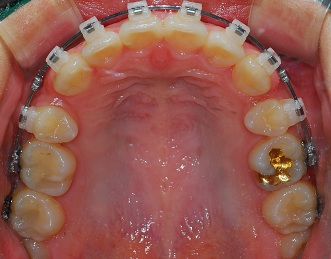

<상악사진>

치료가 굉장히 빨리 진행되시는거 같아요~~ 발치공간 부분이 나날이 쑥쑥 들어가는거 같네요~